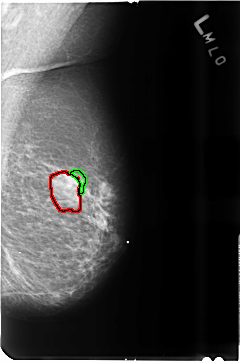

B_3515_1.LEFT_MLO

FILE: B_3515_1.LEFT_MLO.OVERLAY

TOTAL_ABNORMALITIES 2

ABNORMALITY 1

LESION_TYPE MASS SHAPE ROUND-OVAL MARGINS CIRCUMSCRIBED-OBSCURED

ASSESSMENT 4

SUBTLETY 4

PATHOLOGY BENIGN

TOTAL_OUTLINES 1

BOUNDARY

ABNORMALITY 2